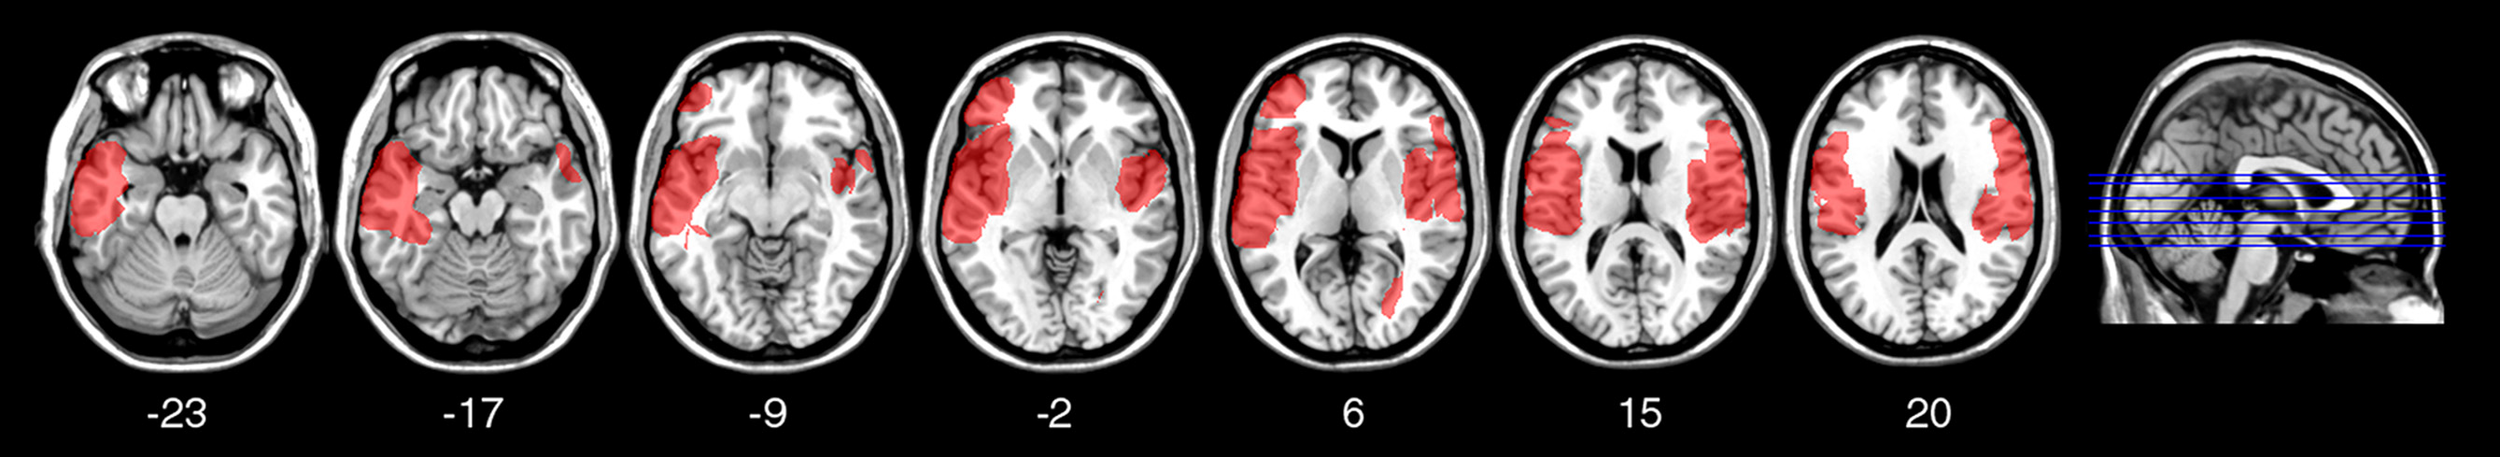

FIGURE 2

Figure 2. Location and overlap of brain lesions in Non-insular patients. The image shows the lesions of the Non-insular patients projected on the same seven axial slices. In each slice, the left hemisphere is on the left side. The level of the axial slices has been marked by white lines on the sagittal view of the brain. The color bar indicates the number of overlapping lesions in the axial slices.

VLSM

To investigate the relation between TD deficits and specific brain lesions, we performed a VLSM analysis. The VLSM analysis related patients’ k rates and AUC values for the Now and Not-now conditions (in separate analyses) to their brain lesions. Figure 6 shows the statistical power map, indicating the voxels where we had adequate power to detect effects with a 5% FDR threshold (Rorden et al., 2007; Gläscher et al., 2010). The brain regions associated with reduced TD, along with the coordinates of their center of mass, based on the MNI brain atlas, are listed in Table 2 and shown in Figure 7.

Figure 6. Statistical power map. Map showing the voxels (in red) where there is sufficient statistical power to detect an effect in this group of patients, overlaid on the MNI brain. In each axial slice, the left hemisphere is on the left side. Z-coordinates of each axial slice are given.